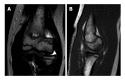

Osteochondritis dissecans (OCD) is a disorder of articular cartilage and subchondral bone. In the elbow, an OCD is localized most commonly at the humeral capitellum. Teenagers engaged in sports that involve repetitive stress on the elbow are at risk. A high index of suspicion is warranted to prevent delay in the diagnosis. Plain radiographs may disclose the lesion but computed tomography and magnetic resonance imaging are more accurate in the detection of OCD. To determine the best treatment option it is important to differentiate between stable and unstable OCD lesions. Stable lesions can be initially treated nonoperatively with elbow rest or activity modification and physical therapy. Unstable lesions and stable lesions not responding to conservative therapy require a surgical approach. Arthroscopic debridement and microfracturing has become the standard initial procedure for treatment of capitellar OCD. Numerous other surgical options have been reported, including internal fixation of large fragments and osteochondral autograft transfer. The aim of this article is to provide a current concepts review of the etiology, clinical presentation, diagnosis, treatment, and outcomes of elbow OCD.